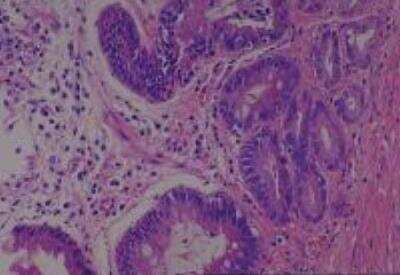

Hematoxylin & Eosin Stain: Human Common Tissue MicroArray (Normal Adjacent) [NBP2-30215] - 01. Stomach